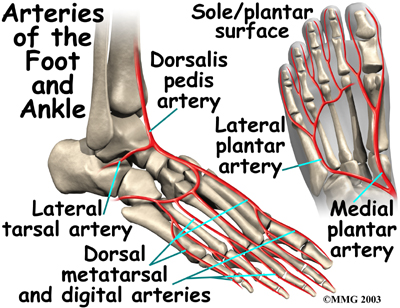

Blood Vessels

The ankle gets blood from nearby arteries that pass by the ankle on their way to the foot. The dorsalis pedis runs in front of the ankle to the top of the foot. (You can feel your pulse where this artery runs in the middle of the top of the foot.) Another large artery, called the , runs behind the medial malleolus. It sends smaller blood vessels to the inside edge of the ankle joint. Other less important from other directions also supply blood to the ankle.